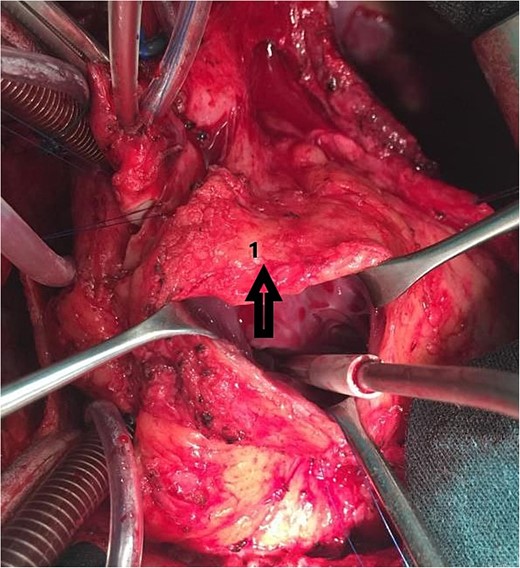

An 11-year-old girl was referred to our hospital with a main complaint of progressive exertional dyspnea. She had undergone surgical repair of SAS 6 years ago. Transthoracic echocardiogram (TTE) revealed the following findings: severe left ventricular hypertrophy, tunnel-like fibromembranous subaortic stenosis with a length of 10 mm, a peak gradient (PG) across the LVOT of 170 mmHg, and mild aortic regurgitation. Based on these findings, the patient was scheduled for elective surgical repair with a possible indication for MKO. The operation was performed via median sternotomy with great caution to avoid inadvertent rupture of any cardiac cavity due to heavy adhesions from the previous operation. The aorta was cannulated just below the takeoff of the innominate artery. Bicaval cannulation was performed to provide a bloodless field. Aortic cross-clamping was applied, and antegrade cold blood cardioplegic solution was administered via a catheter placed in the ascending aorta. The ascending aorta was opened transversely 1 cm above the sinotubular junction (Fig. 1). The aortic valve leaflets were examined carefully to confirm that the aortic valve could be preserved. LVOT was examined thoroughly, and it was clear that the stenosis in the subaortic area was so complex that simple resection through the aortic valve orifice would not be sufficient. The right ventricular outflow tract was opened transversely below the pulmonary valve. The conal papillary muscle was identified (Fig. 2). A right-angle instrument was introduced through the aortic orifice into the interventricular septum, and the tip of the instrument was used to perforate the conal septum to the left of the conal papillary muscle to prevent damage to the conduction system; the septal incision was completed with great caution to avoid damage to the aortic cusps and to extend the incision downward as necessary to completely relieve the stenotic subaortic area (Fig. 3). Interrupted 5/0 Prolene sutures were placed circumferentially around the septal incision to close the interventricular septal defect using a bovine pericardial patch to provide adequate widening of LVOT (Fig. 4). The right ventriculotomy was closed with a second bovine pericardial patch to avoid any possible obstruction of the right ventricular outflow tract (Fig. 5). The remainder of the operation was completed uneventfully. After 6 hours of mechanical ventilation, the patient was extubated, and she convalesced well postoperatively. TTE showed excellent results of the operation with PG across LVOT of 20 mmHg. On 1 year follow-up, the patient was asymptomatic and in very good general condition, and TTE findings confirmed the excellent result.

Intraoperative image showing the bovine pericardial patch used to close the septal incision. (1) Right ventriculotomy and (2) bovine pericardial patch.